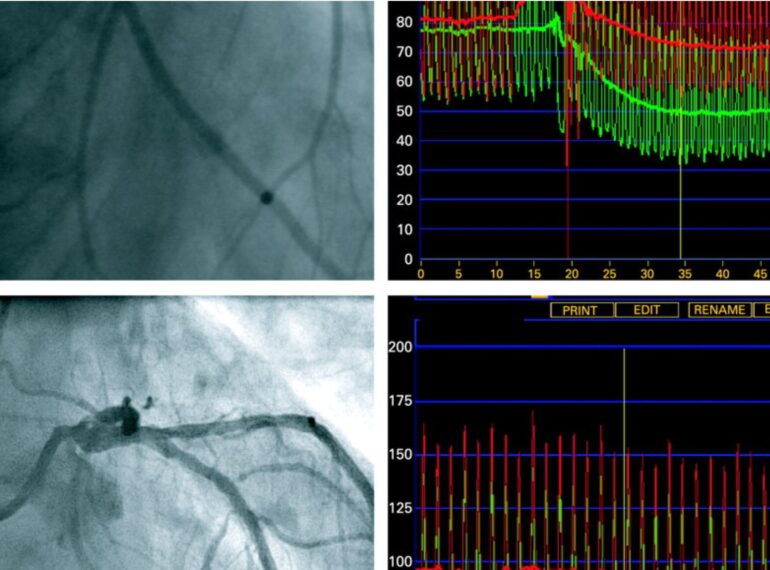

FFR-Guided PCI

Dr. Honey Sharma provides advanced hospital-based cardiac care using the latest techniques and technologies. From angioplasties to device implantations, each procedure is handled with precision and compassion by a super-specialized expert in interventional cardiology.

Radial angioplasty offers faster recovery, less discomfort, and a lower risk of bleeding compared to traditional groin access.